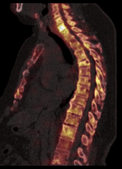

1. Improved imaging results. Through hybrid xSPECT/CT technology, our bone cancer scan is clinically useful compared to SPECT alone because of improved anatomic localisation and diagnostic certainty.

SJMC SPECT Scan Imaging SPECT Only